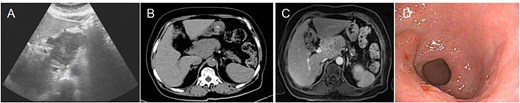

A 74-year-old female patient with a 15-year history of diabetes presented with uninduced foot numbness that began 6 months ago and worsened 1 week prior to admission. Upon hospitalization, a mass was identified in the upper abdomen. Laboratory tests revealed a blood glucose level of 6.80 mmol/l, neuron-specific enolase (NSE) at 18.34 ng/ml, carcinoembryonic antigen (CEA) at 9.69 ng/ml, and a white blood cell count of 10.0 × 109/l. An abdominal computed tomography (CT) showed a mass in the pancreatic head, suspected to be a neuroendocrine tumor, with malignancy not excluded, along with retroperitoneal lymph node enlargement and atrophy of the pancreatic body and tail; the patient had a history of gallbladder surgery. Pancreatic enhanced magnetic resonance imaging (MRI) (3.0T) confirmed an occupying lesion in the pancreatic head, suggesting a neuroendocrine tumor, with malignancy to be ruled out. Electronic gastroscopy indicated chronic atrophic gastritis and revealed a 2.5 × 2.0 cm flat hyperplastic lesion on the anterior wall of the gastric antrum and along the greater curvature (Fig. 1).

Preoperative imaging and endoscopic findings. (A) Abdominal ultrasound identified a space-occupying lesion located in the upper abdominal region. (B) Abdominal CT scan reveals a mass located in the head of the pancreas. (C) 3.0T MRI with contrast enhancement revealed a mass located in the pancreatic head, indicating a potential malignant lesion. (D) Electronic gastroscopy showed chronic atrophic gastritis and antrum bulge.